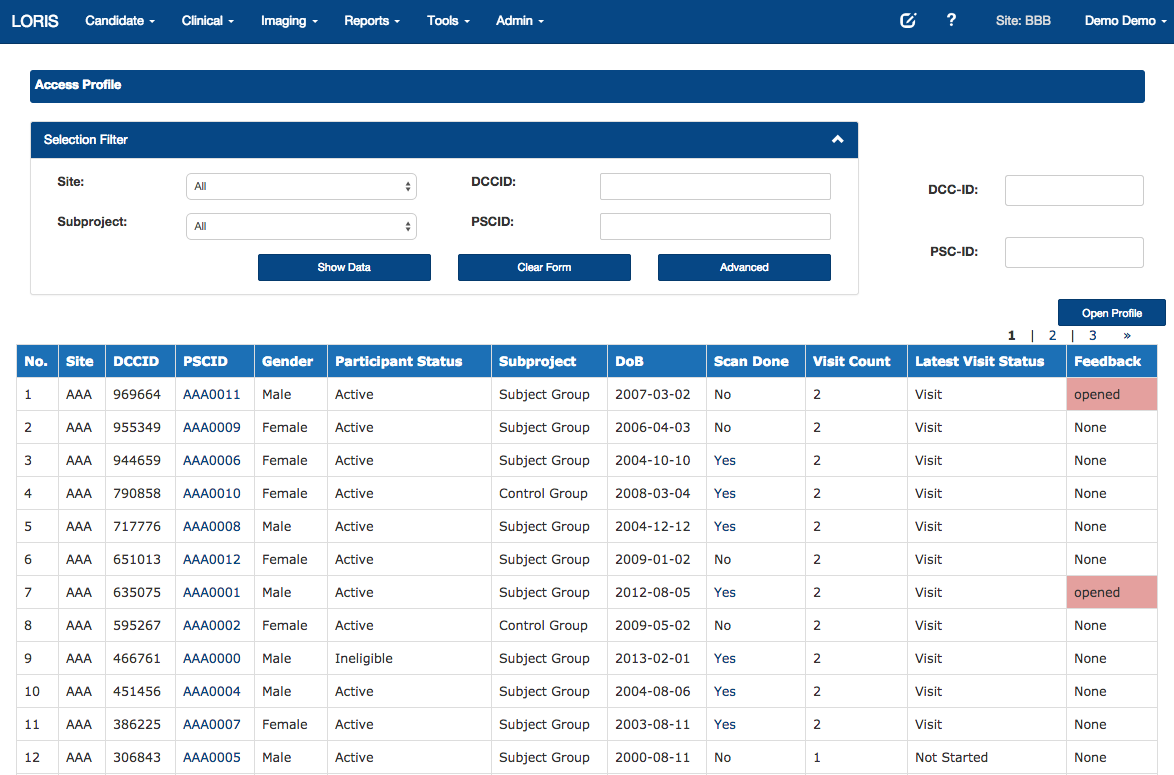

List of subjects